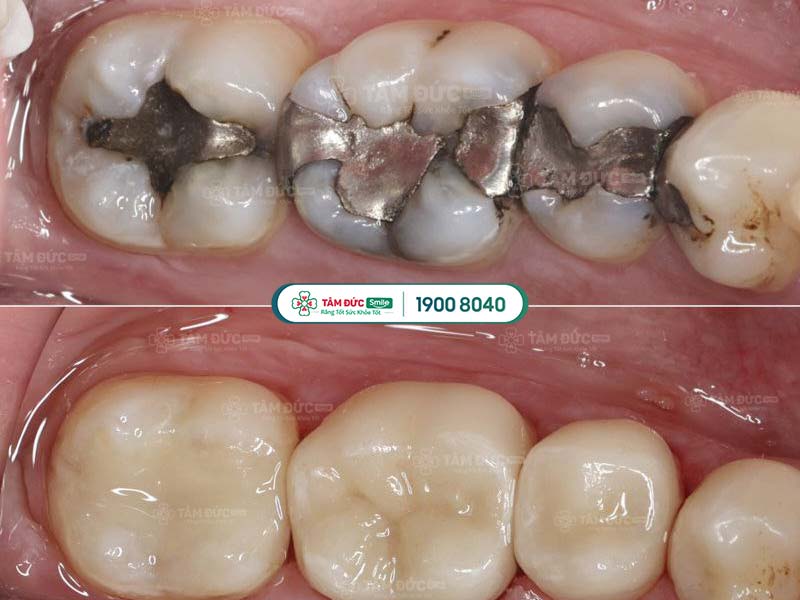

1.4. Thay miếng trám mới

Hiệu quả trám răng không thể duy trì vĩnh viễn. Theo thời gian, miếng trám răng cũ có thể bị bong tróc hoặc rơi ra do tác động từ lực ăn nhai. Trong trường hợp này, bác sĩ sẽ yêu cầu thay miếng trám răng mới.

Quý khách cần trám lại răng khi miếng trám cũ bị bong tróc

Răng được phục hình sau khi trám